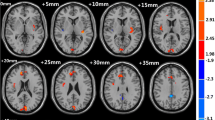

Alterations of ALFF in ID patients

Compared with HCs, ID patients had significantly increased ALFF in the left insula (p = 0.036) and right amygdala (p = 0.039), as well as decreased ALFF in the right SPL (p = 0.005) at the threshold we set (cluster-level p < 0.05, FDR corrected) (Table 3; Fig. 2).

Cortical areas of increased/decreased ALFF in ID patients compared with HC. The red color shows increased spontaneous functional activity in the right amygdala and the left insula in ID patients. The bule color shows decreased spontaneous functional activity in the right superior parietal lobule in insomnia patients. SPL, superior parietal lobule; L, left; R, right

Alterations of seed-based FC in ID patients

The center points of the peak t value in brain regions that showed significant differences in ALFF between ID patients and HCs (left insula, right amygdala, and right SPL) were defined as spherical ROIs (r = 3 mm). The FC analysis revealed increased connectivity between the left insula and bilateral precentral (Table 4; Fig. 3) and increased connectivity between the right amygdala and left PCC in the ID patients (FDR correction, p < 0.05) (Table 4; Fig. 4). However, ID patients failed to reveal any suprathreshold clusters between the ROI of the right SPL and the whole brain regions.